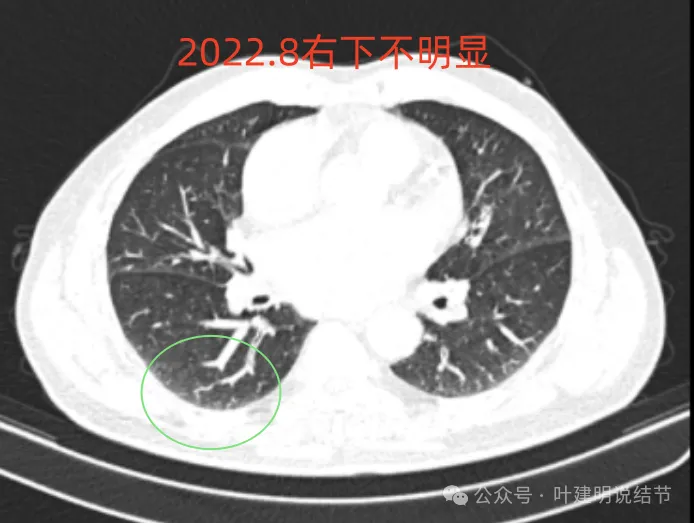

右下似见微小结节,实性,与边上小血管截面不太好区分,过小没什么临床意义,能随访。

多是微小实性结节,主要的仍是右上与左下的这两处,较3月时无明显变化。而右下原来似有微小结节处这次并不明显。